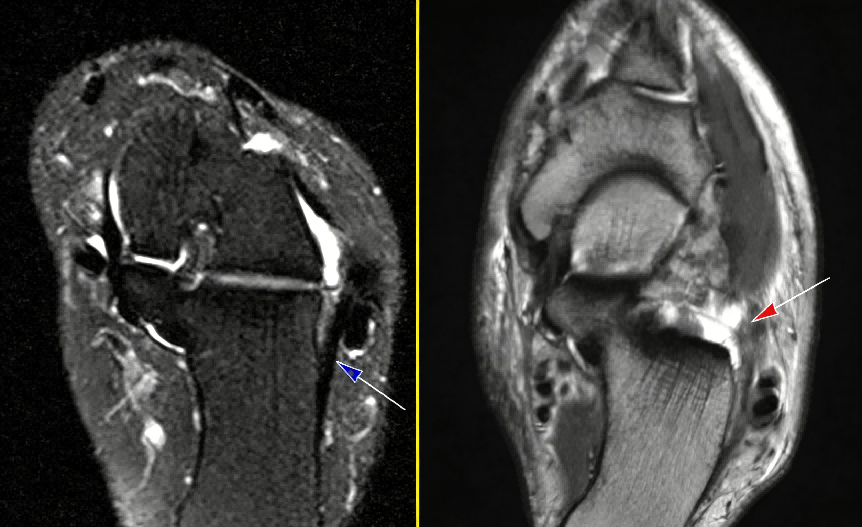

MRI(核心):清晰显示韧带撕裂部位、程度,同步评估周围软组织及合并损伤。